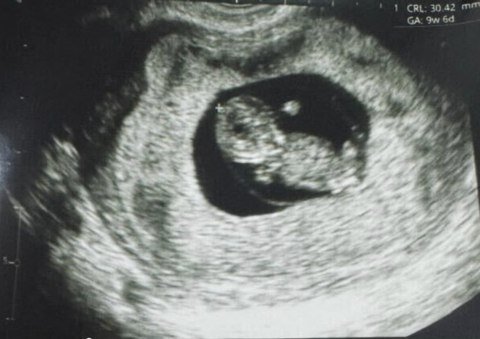

Этот малыш уже стал объектом особого внимания, а новость о его рождении распространилась благодаря американской биотехнологической компании Gameto, которая занимается развитием методов улучшения женского здоровья. Ребёнок был зачат с использованием инновационной технологии Fertilo, представляющей собой разновидность экстракорпорального оплодотворения (ЭКО). Этот метод позволяет созревание яйцеклетки проводить вне тела женщины с использованием поддерживающих клеток яичников, которые в лабораторных условиях получают из стволовых клеток.